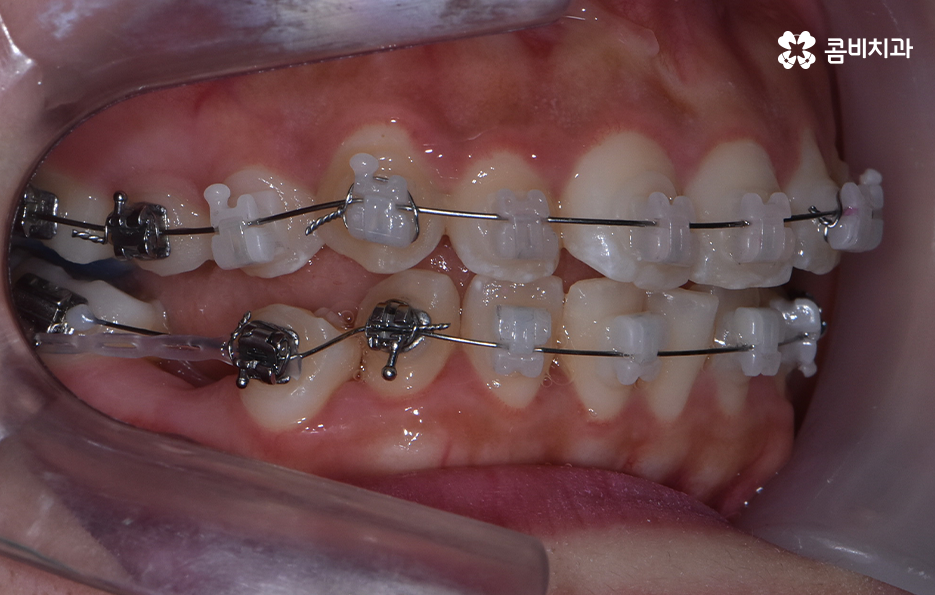

덧니가 심하지 않은 경우에는 비발치로도 충분히 교정을 하는 경우도 있겠지만 덧니가 심한 경우에는 덧니 발치 교정을 통해서 치료가 진행되는 경우가 많이 있는데요. 그 이유는 치아교정의 원리를 생각하더라도 치아를 재배치하기 위해서는 기존의 치아가 움직일 공간이 필요한데 덧니는 치열이 이미 완성되고 있는 상태에서 치아가 나올 공간이 부족하여 덧니가 되는 경우가 많다는 점에서도 치아의 이동 공간을 확보하기 위한 발치가 필요할 수 있는 거예요

물론 치아의 이동 공간을 조금만 확보하면 되는 경우에는 악궁 확장이나 치간 삭제와 같은 방법으로도 치아의 이동 공간을 확보하여 비발치로 치아교정이 가능한 사례도 있지만 덧니 교정을 통해서 부정교합과 함께 얼굴형의 변화까지 치료 목적으로 하는 경우에는 발치가 필요한 경우가 많다고 볼 수 있어요

물론 덧니 발치 교정을 하는 사례가 보편적으로 많은 편이긴 하지만 무조건 발치 교정이 좋은 것은 아니고 꼭 해야 하는 것은 아니라고 할 수 있는데요. 앞서 설명드린 것처럼 치아 공간 확보가 충분히 되는 경우도 있고 얼굴형과 입술 라인을 고려할 때 발치를 하는 것이 얼굴과의 조화 부분에서 더 이로울 것으로 예상되는 경우와 발치 후 합죽이와 같이 보이는 안좋은 결과가 예상된다면 무리한 발치는 안하는 것이 좋다고 볼 거예요